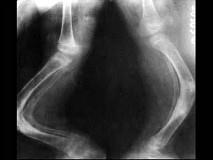

问题 女,2岁,发现蓝色巩膜、听力障碍,四肢畸形等,结合图像,最可能诊断是?(?)

选项 A.维生素D缺乏病 B.维生素C缺乏症 C.软骨发育不全 D.呆小病 E.成骨不全

答案 E